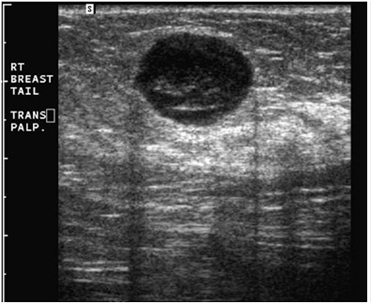

β) Για να διερευνήσουμε τη σύσταση ενός ογκιδίου, συμπαγούς ή κυστικής μορφής (εικόνες 1,2,3) που ψηλαφάται ή φαίνεται μαστογραφικά και να πάρουμε περισσότερες πληροφορίες γι’ αυτό (περίγραμμα, μέγεθος, απόσταση από το δέρμα, αγγείωση).

(Εικόνα 1: Υπερηχογραφική εικόνα ινοαδενώματος (καλοήθους όγκου) του μαστού)

(Εικόνα 2: Υπερηχογραφική εικόνα κύστεως του μαστού)

(Εικόνα 3: Υπερηχογραφική εικόνα νεοεξεργασίας (καρκίνου) του μαστού)